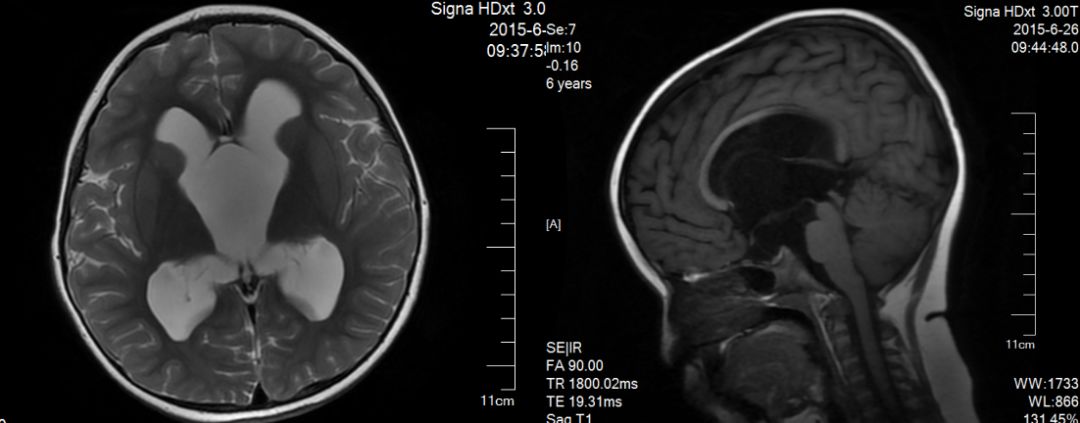

取右侧脑室额角常规入路,进入侧脑室后,拔除,导入内镜。确认室间孔及三脑室内囊肿。电凝囊肿壁及其上血管,并使其皱缩,并切除部分囊肿壁造瘘,经瘘口探查三脑室底,见囊肿底部疝入桥前池水平,明确可见漏斗、鞍背、动眼神经、基底动脉及分支、桥脑等结构。于鞍背与桥脑之间分离囊壁及粘连的蛛网膜与liliquist膜造瘘6mm大小。见脑脊液搏动良好。